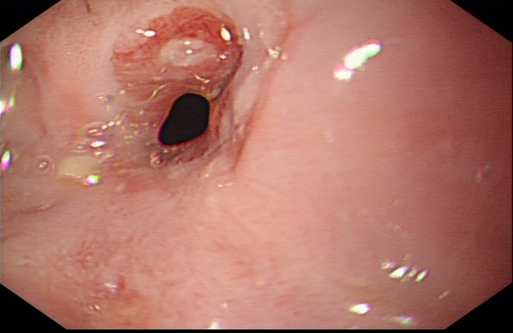

食管癌内镜表现

扩张前食管吻合口明显狭窄